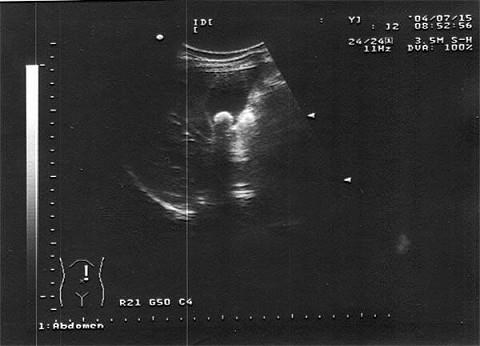

女,36岁,上腹疼痛不适二年余。结合超声声像图,诊断为?(?)A.胆囊息肉B.胆囊胆汁淤积C.胆囊结石D.胆囊癌E.胆囊腺瘤

问题 女,36岁,上腹疼痛不适二年余。结合超声声像图,诊断为?(?)

选项 A.胆囊息肉 B.胆囊胆汁淤积 C.胆囊结石 D.胆囊癌 E.胆囊腺瘤

答案 C